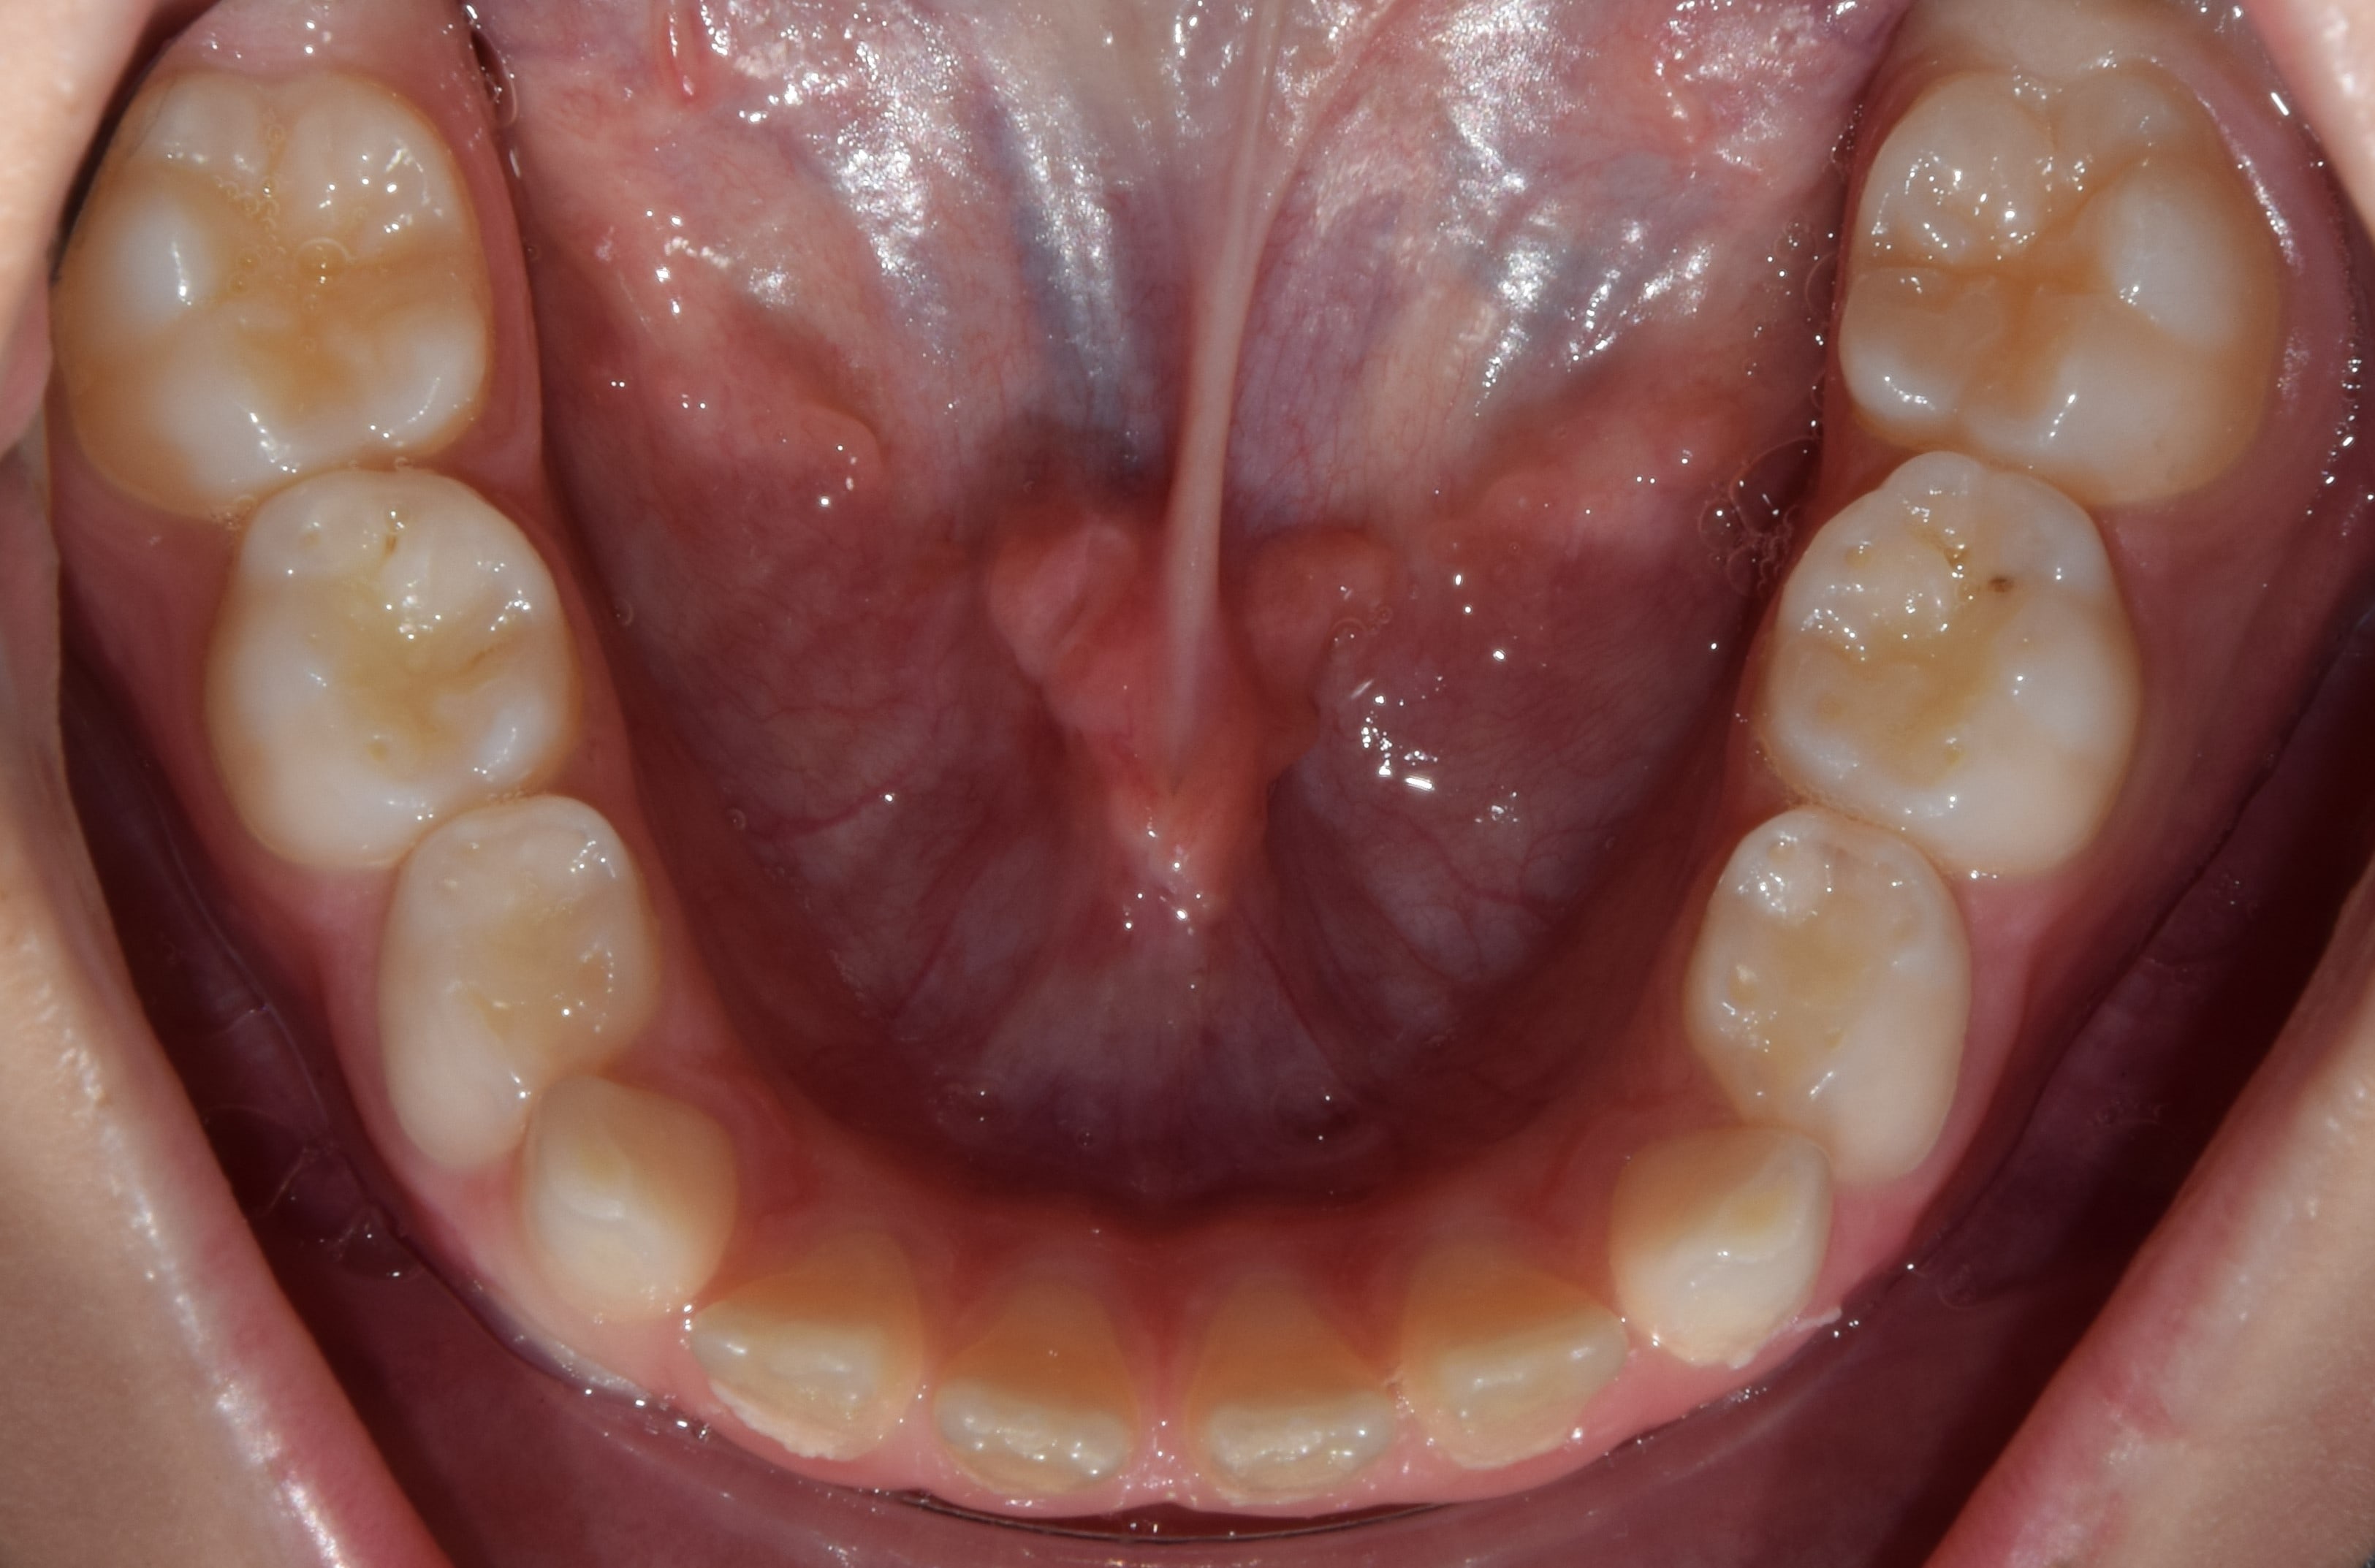

Korai vegyesfogazat

7-8 éves kor körül a gyermekek többségének korai vegyesfogazata van. Ez azt jelenti, hogy az első maradó nagyőrlők előtörtek, a tej metszőfogakat pedig felváltották a maradó metszőfogak.

Késői vegyesfogazat

10-11 éves korban beszélünk késői vegyesfogazatról, amikor megkezdődik az oldalsó tejfogak elvesztése, és a tej őrlők, tejszemfogak helyére nőnek a maradó kisőrlők és szemfogak. Késői vegyesfogazatban a szájüregben eltérő sorrendben nőnek a maradófogak, illetve esnek ki a tejfogak.

Torlódott fogazat

A legtöbbször panaszt okozó fogszabályozási kórkép. Számos oka lehet a fogtorlódások kialakulásának. Előfordulhat, hogy a fogak mérete jóval nagyobb, mint az állcsontok által biztosított hely. Bizonyos esetekben a fogak nyelv felé való dőlése miatt szűkül be a fogív, és emiatt a szűkebb íven csak torlódva férnek el a fogak. Fontos a torlódás okának pontos feltárása, hiszen sikeres kezelést csak így végezhetünk.